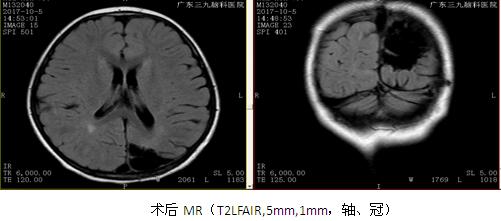

讨论:患者发作间歇期及发作期均为双侧弥漫性放电,但后头部明显,考虑局灶性癫痫,患者颅内多发病灶,考虑症状性局灶性癫痫,患儿有皮肤色素脱失斑,影像学有脑皮层发育不良,符合2012年结节性硬化专家共识的结节性硬化诊断标准。患者多种抗癫痫药物无效,考虑外科手术治疗,有研究表明:钙化结节和最大结节很有可能是结节性硬化患者的致痫结节,手术切除能取得良好手术效果,儿童脑发育不完善,局灶性癫痫往往以全部性发作为表现形式,患者发作形式为强直发作,是以全部性发作为表现的局灶性癫痫,结合VEEG、PET-CT最终予左枕内侧面结节切除,术后取得良好的效果,相关文献研究显示:儿童后头部癫痫的症状学,显示了重要的年龄相关性,与成人相比,儿童发作时间更短但更频繁,很少有先兆或视觉感觉症状,偶发复杂运动及全身强直阵挛,而发作微笑,点头和行为改变是典型的特征,强直发作的患者中(SPECT)检查结果在额叶辅助运动区(SMA)的高灌注,考虑后头部癫痫向前传导至SMA可能,还需进一步证实。